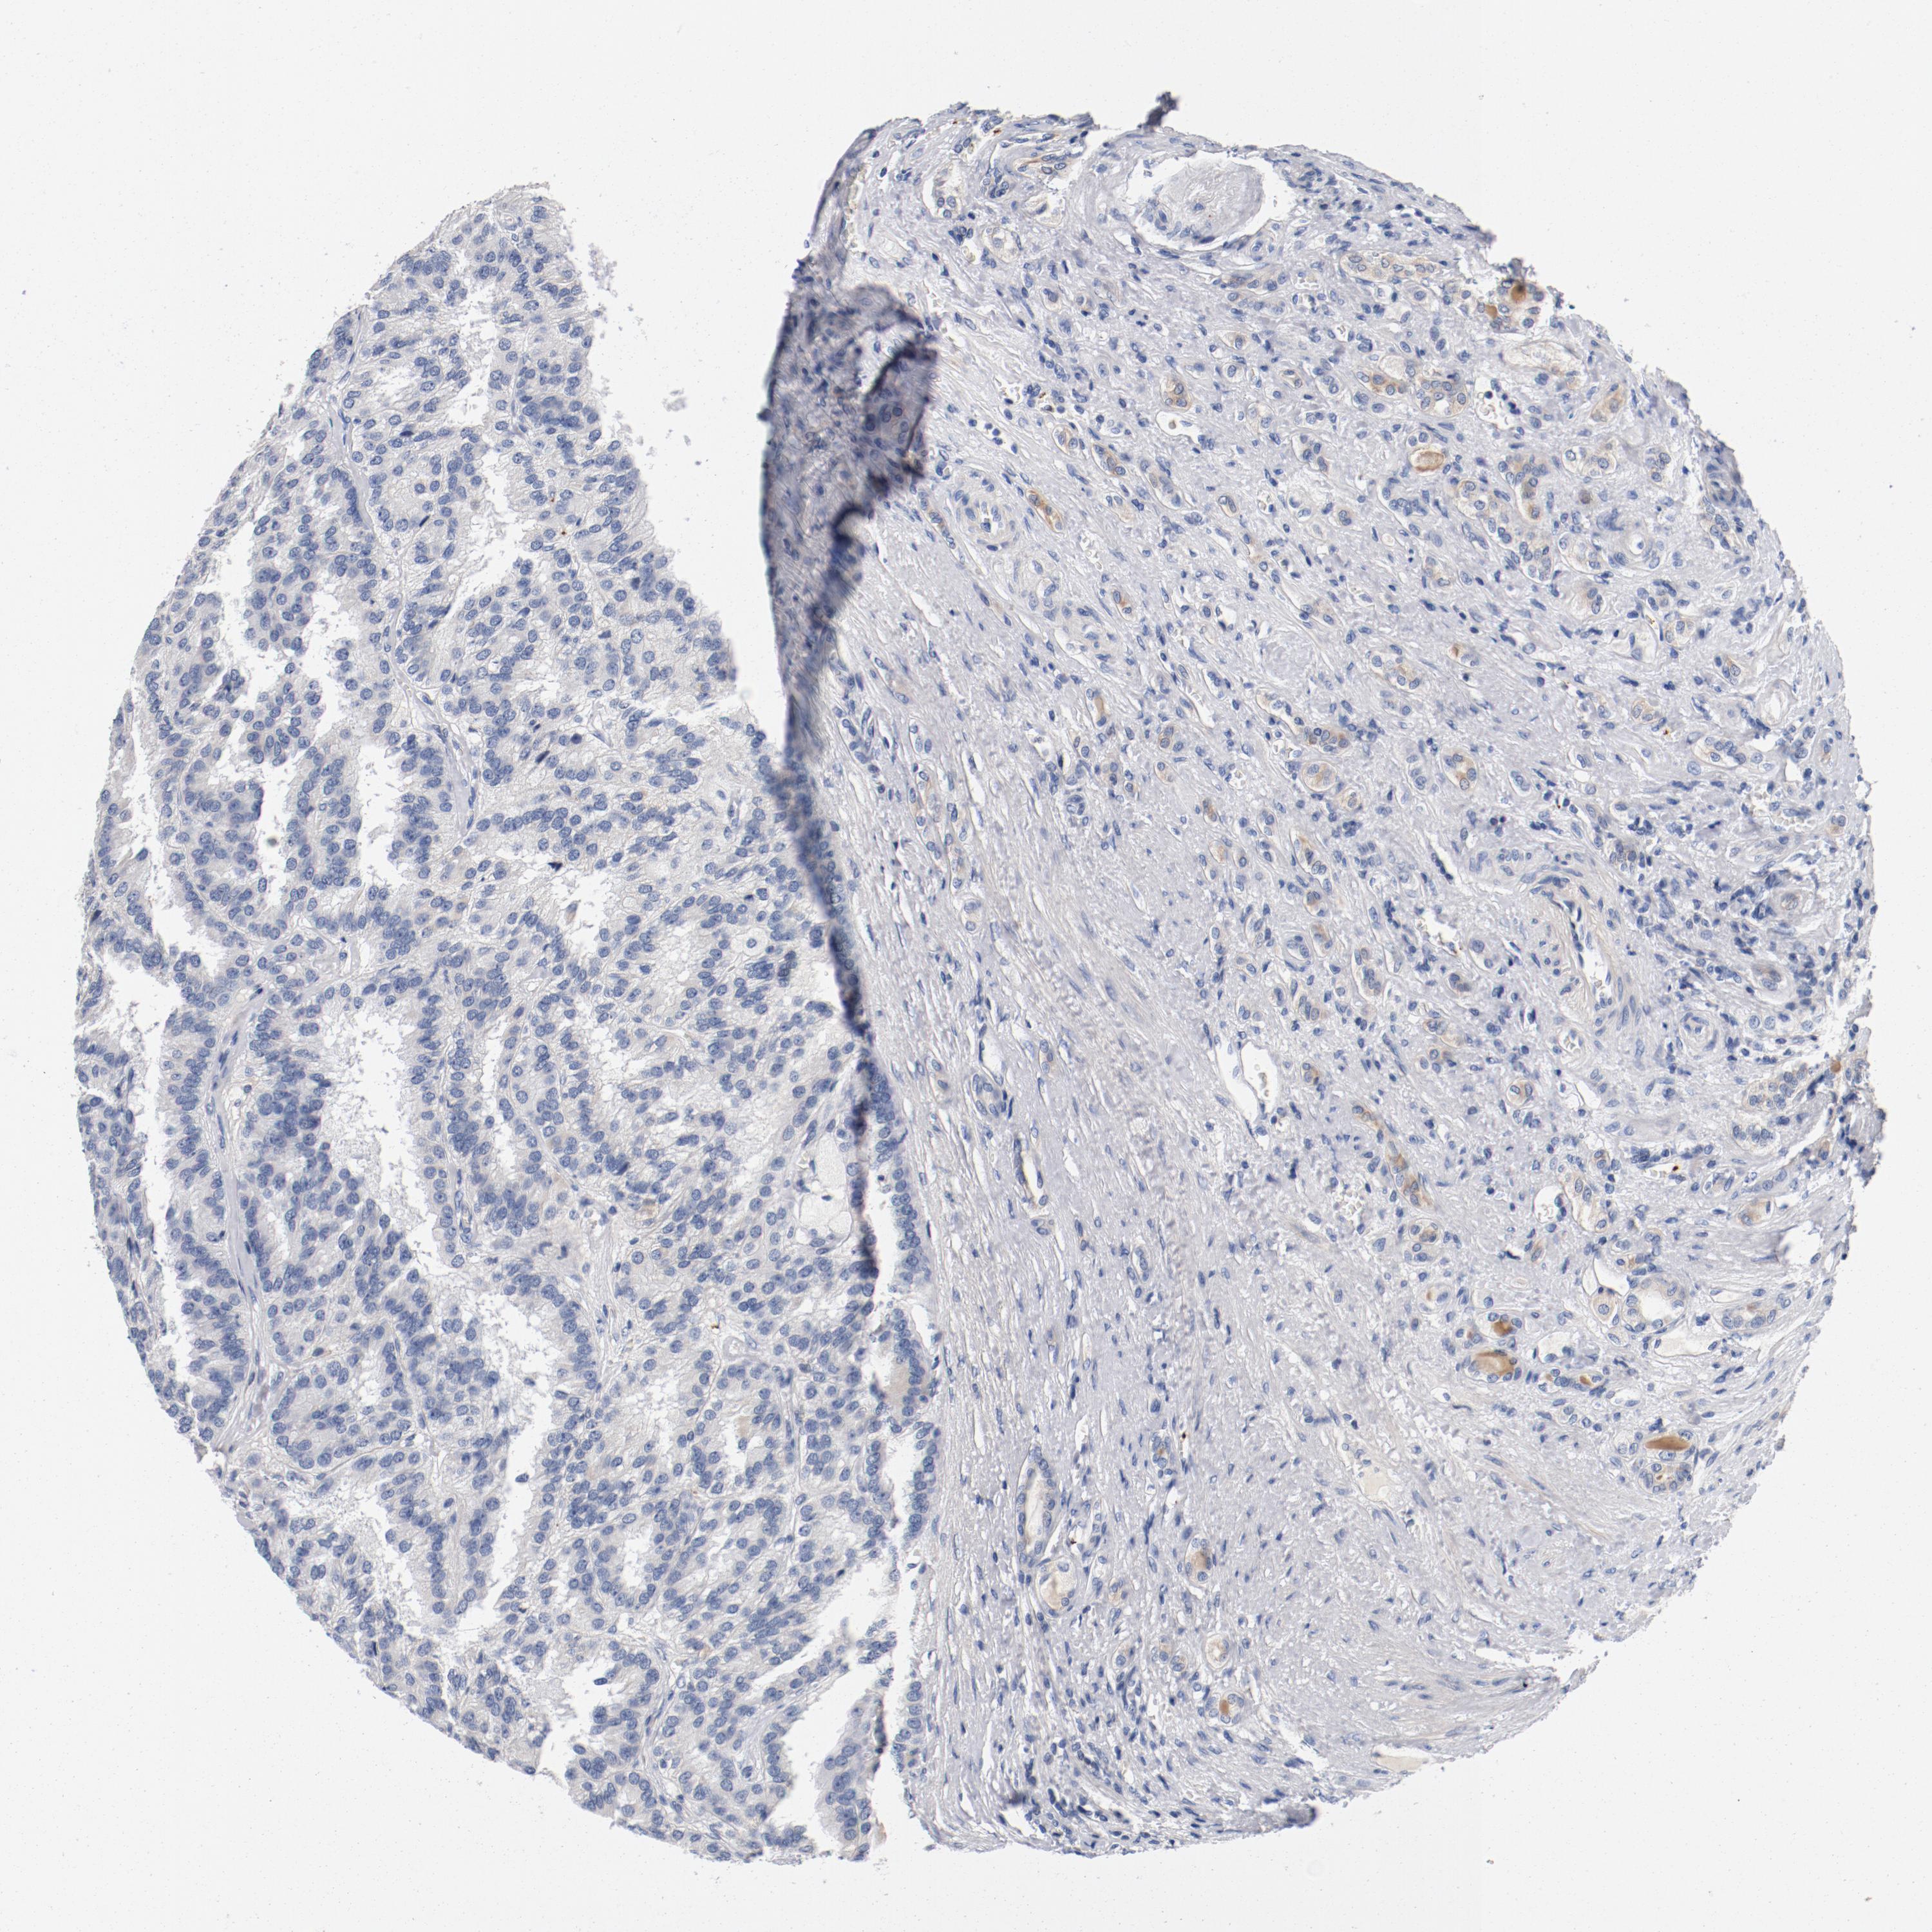

KIDNEY RENAL CLEAR CELL CARCINOMA (VALIDATION) - Interactive survival scatter ploti

The Survival Scatter plot shows the clinical status (i.e. dead or alive) for all individuals in the patient cohort, based on the same data that underlies the corresponding Kaplan-Meier plots. Patients that are alive at last time for follow-up are shown in blue and patients who have died during the study are shown in red.

The x-axis shows the expression levels (FPKM) of the investigated gene in the tumor tissue at the time of diagnosis. The y-axis shows the follow-up time after diagnosis (years). Both axes are complimented with kernel density curves demonstrating the data density over the axes. The top density plot shows the expression levels (FPKM) distribution among dead (red) and alive patients (blue). The right density plot shows the data density of the survived years of dead patients with high and low expression levels respectively, stratified using the cutoff indicated by the vertical dashed line through the Survival Scatter plot. This cutoff is automatically defined based on the FPKM cutoff that minimizes the p-score. The cutoff can be changed by dragging the vertical line or by entering a cutoff value in the square labeled "Current cut-off".

Under the Survival Scatter plot the p-score landscape (black curve; left axis) is shown together with dead median separation (red curve; right axis). Dead median separation is the difference in median mRNA expression between patients who have died with high and low expression, respectively. It is calculated as follows: median FPKM expression of dead patients with high expression - median FPKM expression of dead patients with low expression. This is intended to aid the user in visually exploring custom cutoffs and the associated p-scores and dead median separation.

Individual patient data is displayed and can be filtered by clicking on one or more of the category buttons on the top of the page. Categories describing expression level and patient information include: high, low, alive, dead, female, male and tumor stages. The scale of the x-axis can be toggled between linear and log-scale by clicking on the "x log" button. Mouse-over function shows TCGA ID, patient information and mRNA expression (FPKM) for each patient.

& Survival analysisi

Kaplan-Meier plots summarize results from analysis of correlation between mRNA expression level and patient survival. Patients were divided based on level of expression into one of the two groups "low" (under cut off) or "high" (over cut off). X-axis shows time for survival (years) and y-axis shows the probability of survival, where 1.0 corresponds to 100 percent.

PIM1 is not prognostic in Kidney Renal Clear Cell Carcinoma (validation)

Best expression cut offi

Based on the FPKM value of each gene, patients were classified into two groups and association between prognosis (survival) and gene expression (FPKM) was examined. The best expression cut-off refers the FPKM value that yields maximal difference with regard to survival between the two groups at the lowest log-rank P-value. Best expression cut-off was selected based on survival analysis .

When clicking on this number, the vertical dashed line indicating cut-off, the interactive survival plot, and the Kaplan-Meier curve will be adjusted to show results based on the best expression cut-off.

: 40.13

Median expressioni

Median expression refers to the median FPKM value calculated based on the gene expression (FPKM) data from all patients in this dataset. When clicking on this number, the vertical dashed line indicating cut-off, the interactive survival plot, and the Kaplan-Meier curve will be adjusted to show results based on the median expression.

: N/A

Median follow up timei

Median follow up time refers to the median time (years) after diagnosis with this type of cancer, based on clinical data from all patients in this dataset.

P scorei

Log-rank P value for Kaplan-Meier plot showing results from analysis of correlation between mRNA expression level and patient survival.

N/A

5-year survival highi

5-year survival for patients with higher expression than the expression cutoff.

For melanoma and glioma, 3-year survival is shown.

5-year survival lowi

5-year survival for patients with lower expression than the expression cutoff.

TCGA RNA samplesi

RNA-seq data is reported as average FPKM (number Fragments Per Kilobase of exon per Million reads), generated by the The Cancer Genome Atlas (TCGA) .

Normal distribution across the dataset is visualized with box plots, shown as median and 25th and 75th percentiles. Points are displayed as outliers if they are above or below 1.5 times the interquartile range. FPKM values of the individual samples are presented next to the box plot.

Average pTPM 32.4

Number of samples 100